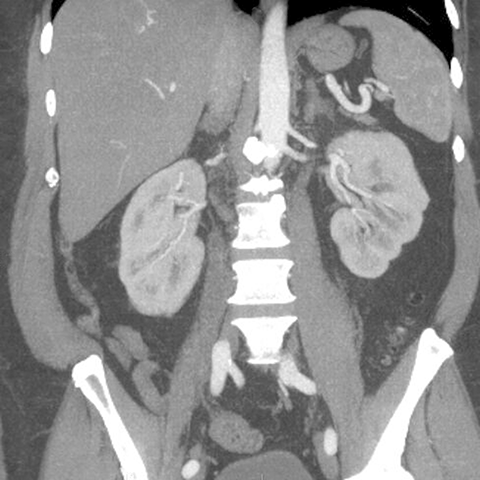

Normal Appendix, CT (coronal) [2 of 6]